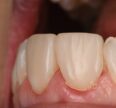

Semi-direct composite crowns completed on indirect A-silicone model after rough crown preparations to remove defective dentin (see pre-op radiograph for extent of caries/compromise due to hypoplastic and hypocalcified variant of Amelogenesis Imperfecta in this 12 year old female.

Model: Voco Die Silicon (A-silicone) : red

Restorative: Voco Grandio SO A2

Tints: Voco Final Touch Brown.